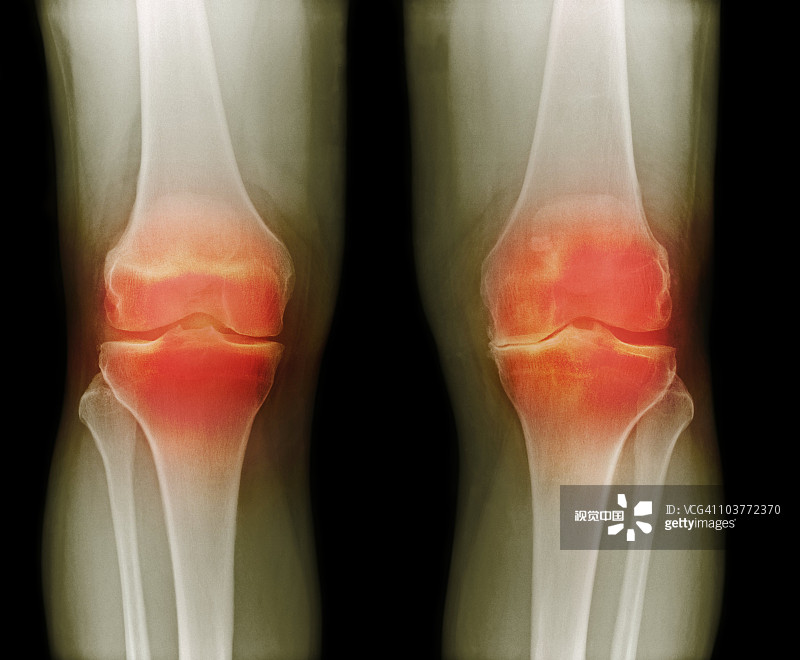

適應(yīng)癥:膝骨關(guān)節(jié)炎

- 2.依據(jù)參考中華醫(yī)學(xué)會骨科學(xué)分會關(guān)節(jié)外科學(xué)組制定的“骨關(guān)節(jié)炎診療指南(2018年版)”,明確診斷為膝骨關(guān)節(jié)炎(KOA)

- 6.受試者研究側(cè)膝關(guān)節(jié)Kellgren-Lawrence分級為II/III級。